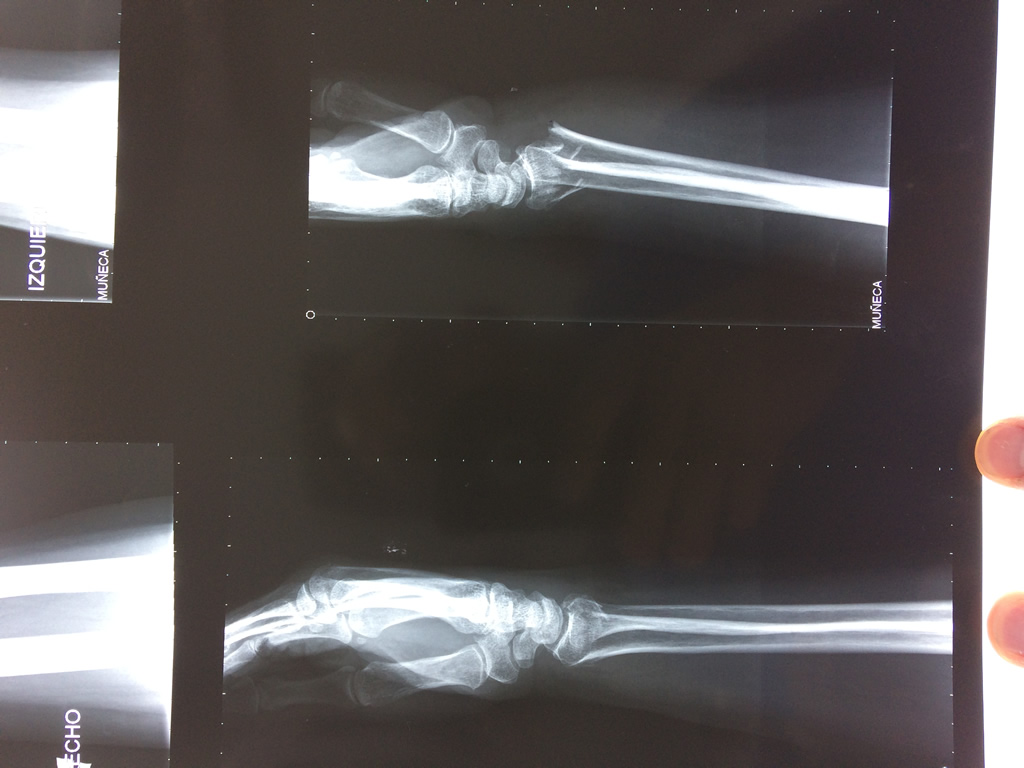

Cirugías de Codo - Cirugías de Muñecas y Manos

Los procedimientos más comunes en cirugía de la mano son aquellos destinados a reparar traumatismos, incluyendo lesiones de tendones, nervios, vasos sanguíneos, y articulaciones; huesos fracturados; y quemaduras, cortes, y otros daños de la piel.